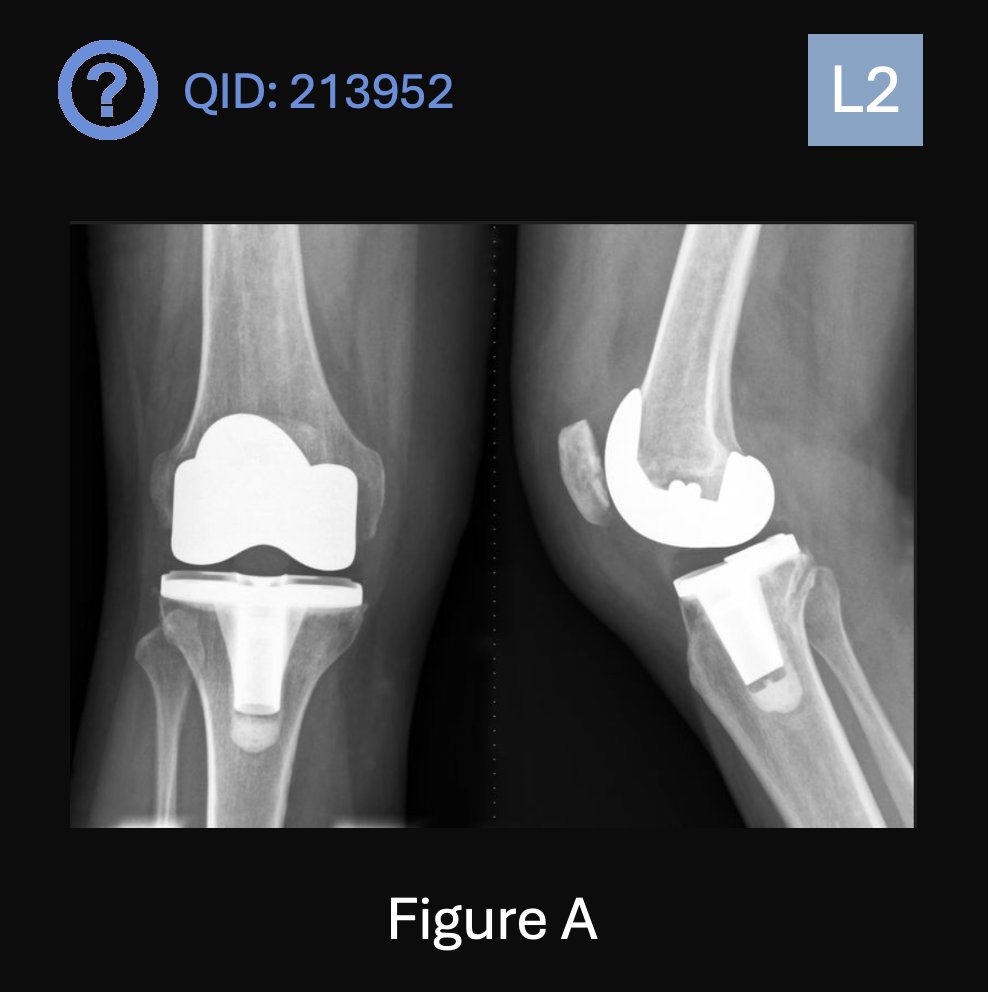

Can you answer our FREE Question of the Day? A 73-year-old undergoes the procedure depicted in Figure A. Which of the following statements below related to his procedure is most accurate? 1. The use of continuous passive motion (CPM) postoperatively correlates with early